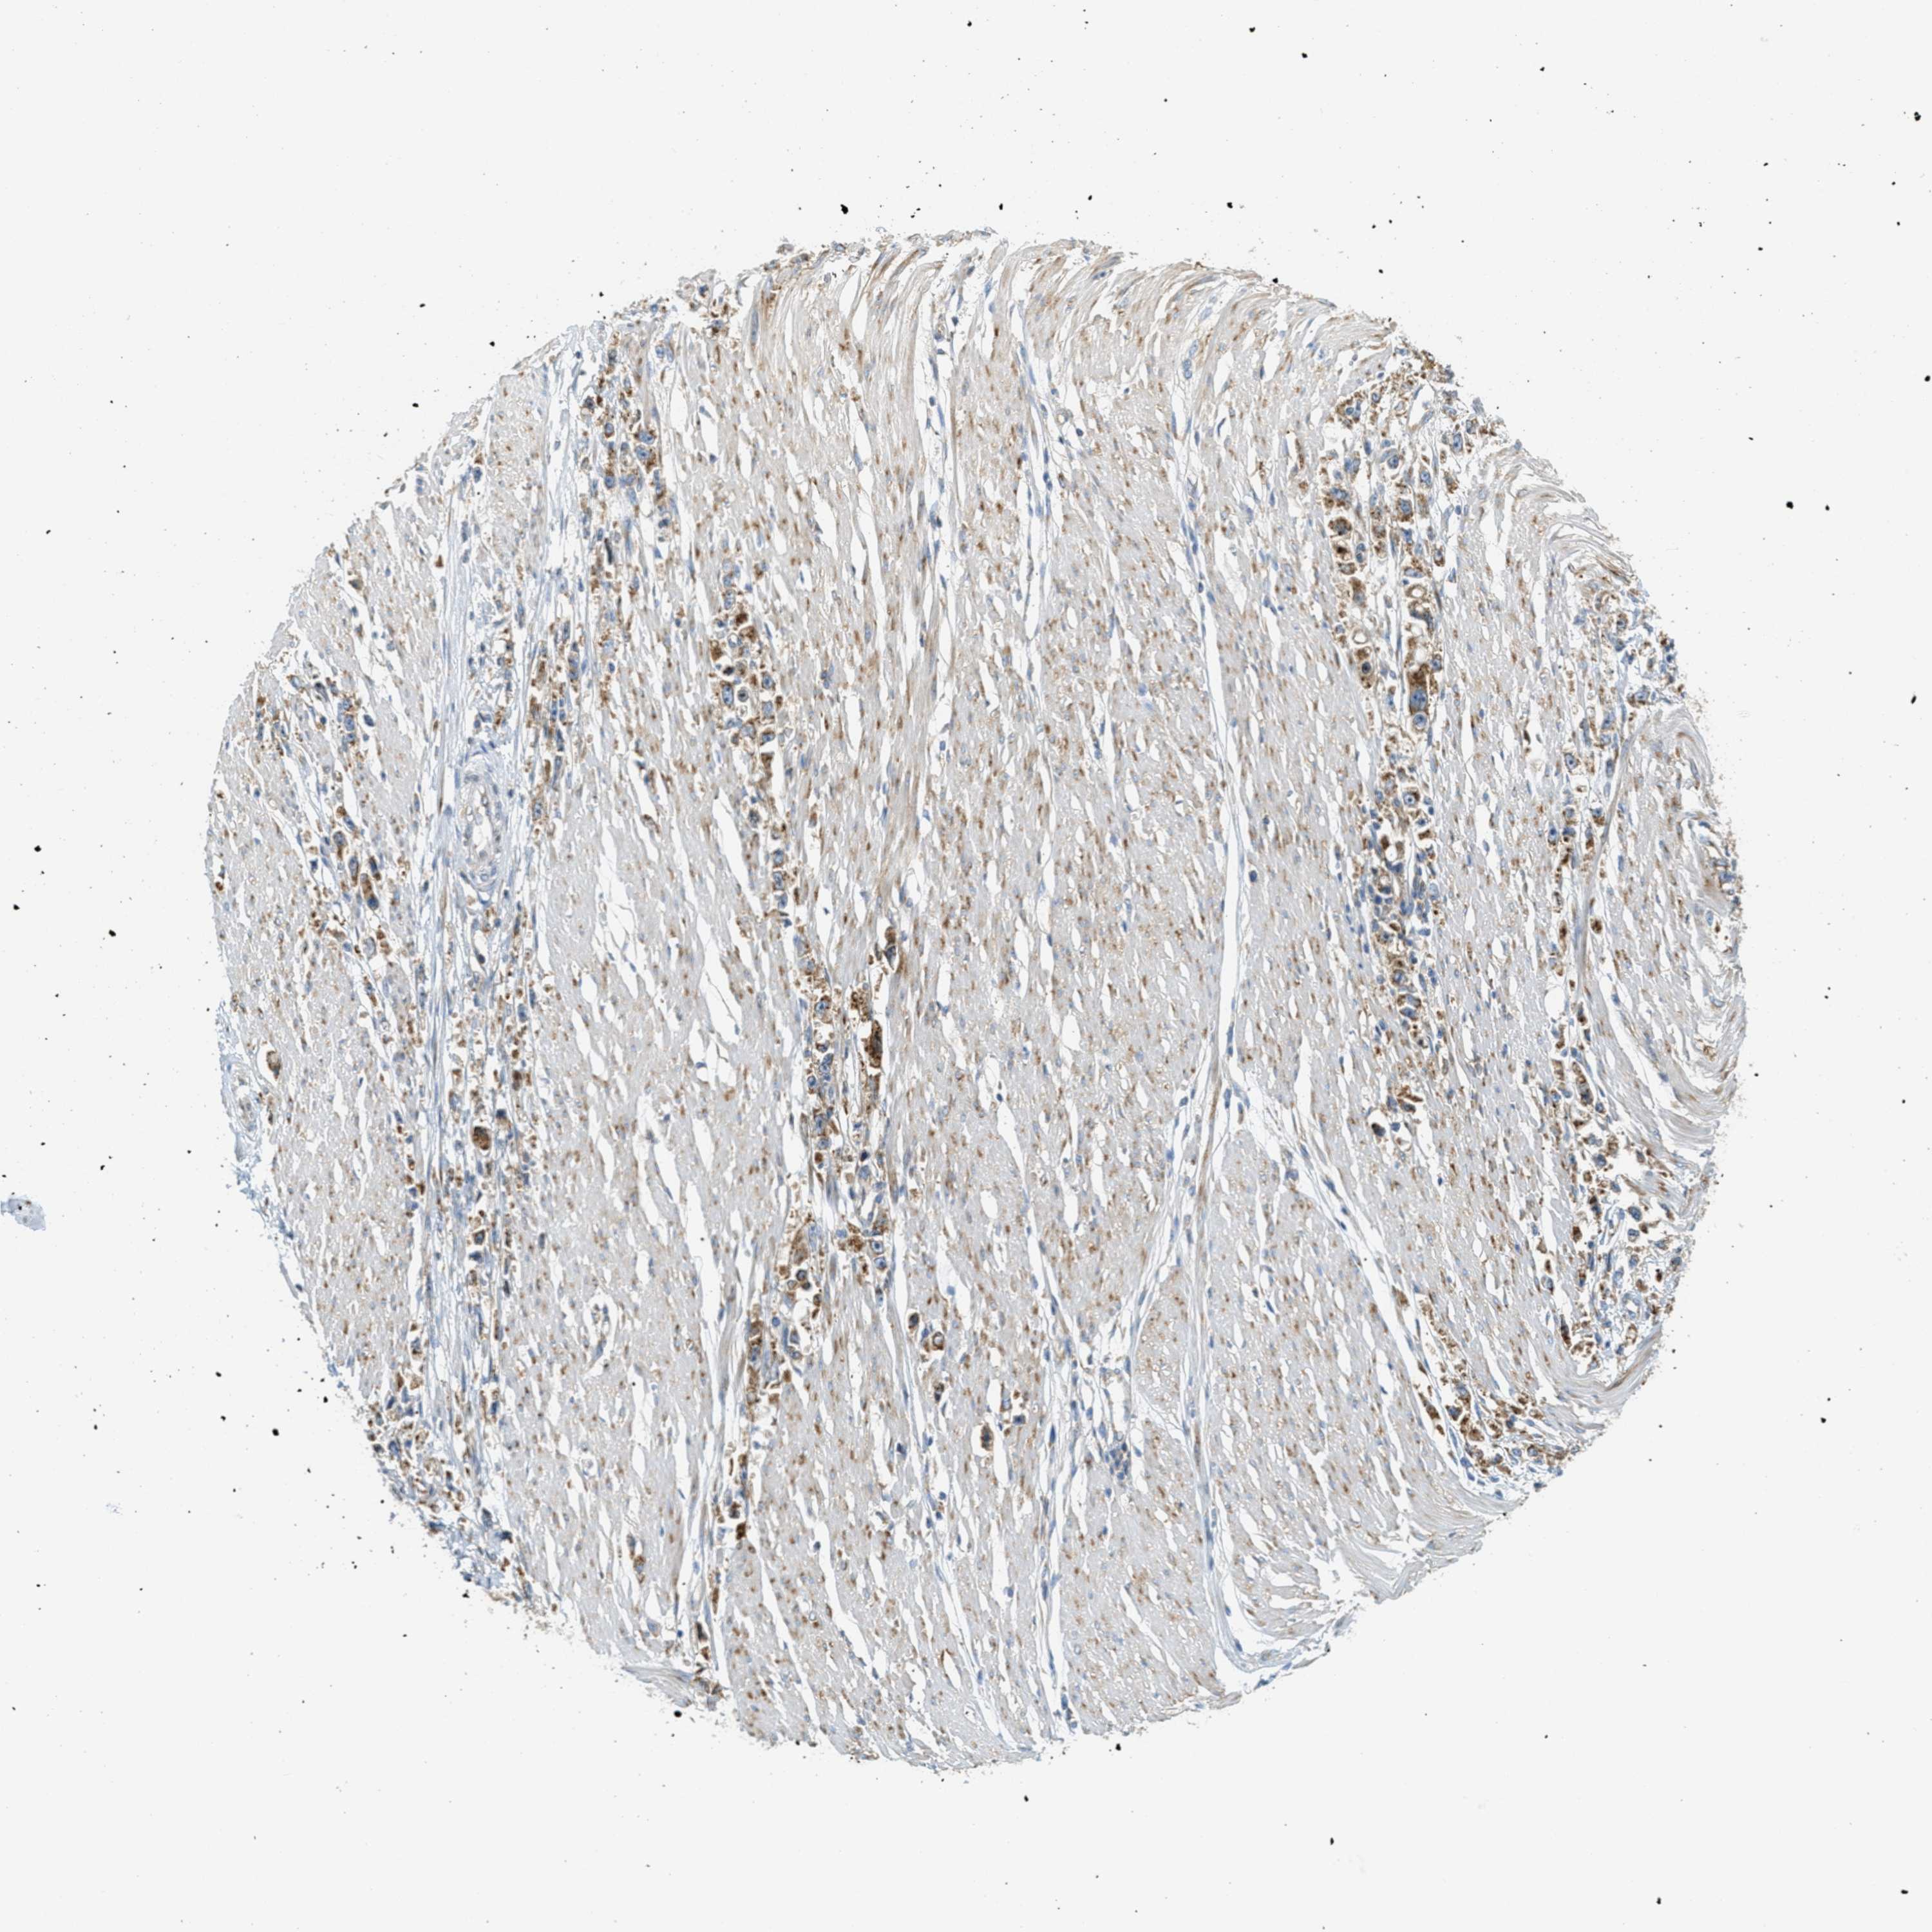

STOMACH CANCER - Protein expressioni

A mouse-over function shows sample information and annotation data. Click on an image to view it in a full screen mode. Samples can be filtered based on level of antibody staining by selecting one or several of the following categories: high, medium, low and not detected. The assay and annotation is described here.

Note that samples used for immunohistochemistry by the Human Protein Atlas do not correspond to samples in the TCGA dataset.

Antibody stainingi

Antibody staining in the annotated cell types in the current human tissue is reported as not detected, low, medium, or high, based on conventional immunohistochemistry profiling in selected tissues. This score is based on the combination of the staining intensity and fraction of stained cells.

Each image is clickable and will lead to virtual microscopy that enables deeper exploration of all samples and also displays staining intensity scores, fraction scores and subcellular localization as well as patient and tissue information for each sample.

Antibody HPA017578

Staining

High

Medium

Low

Not detected

Intensity

Strong

Moderate

Weak

Negative

Quantity

>75%

75%-25%

<25%

None

Location

Nuclear

Cytoplasmic/membranous

Cytoplasmic/membranous,nuclear

Adenocarcinoma, NOS